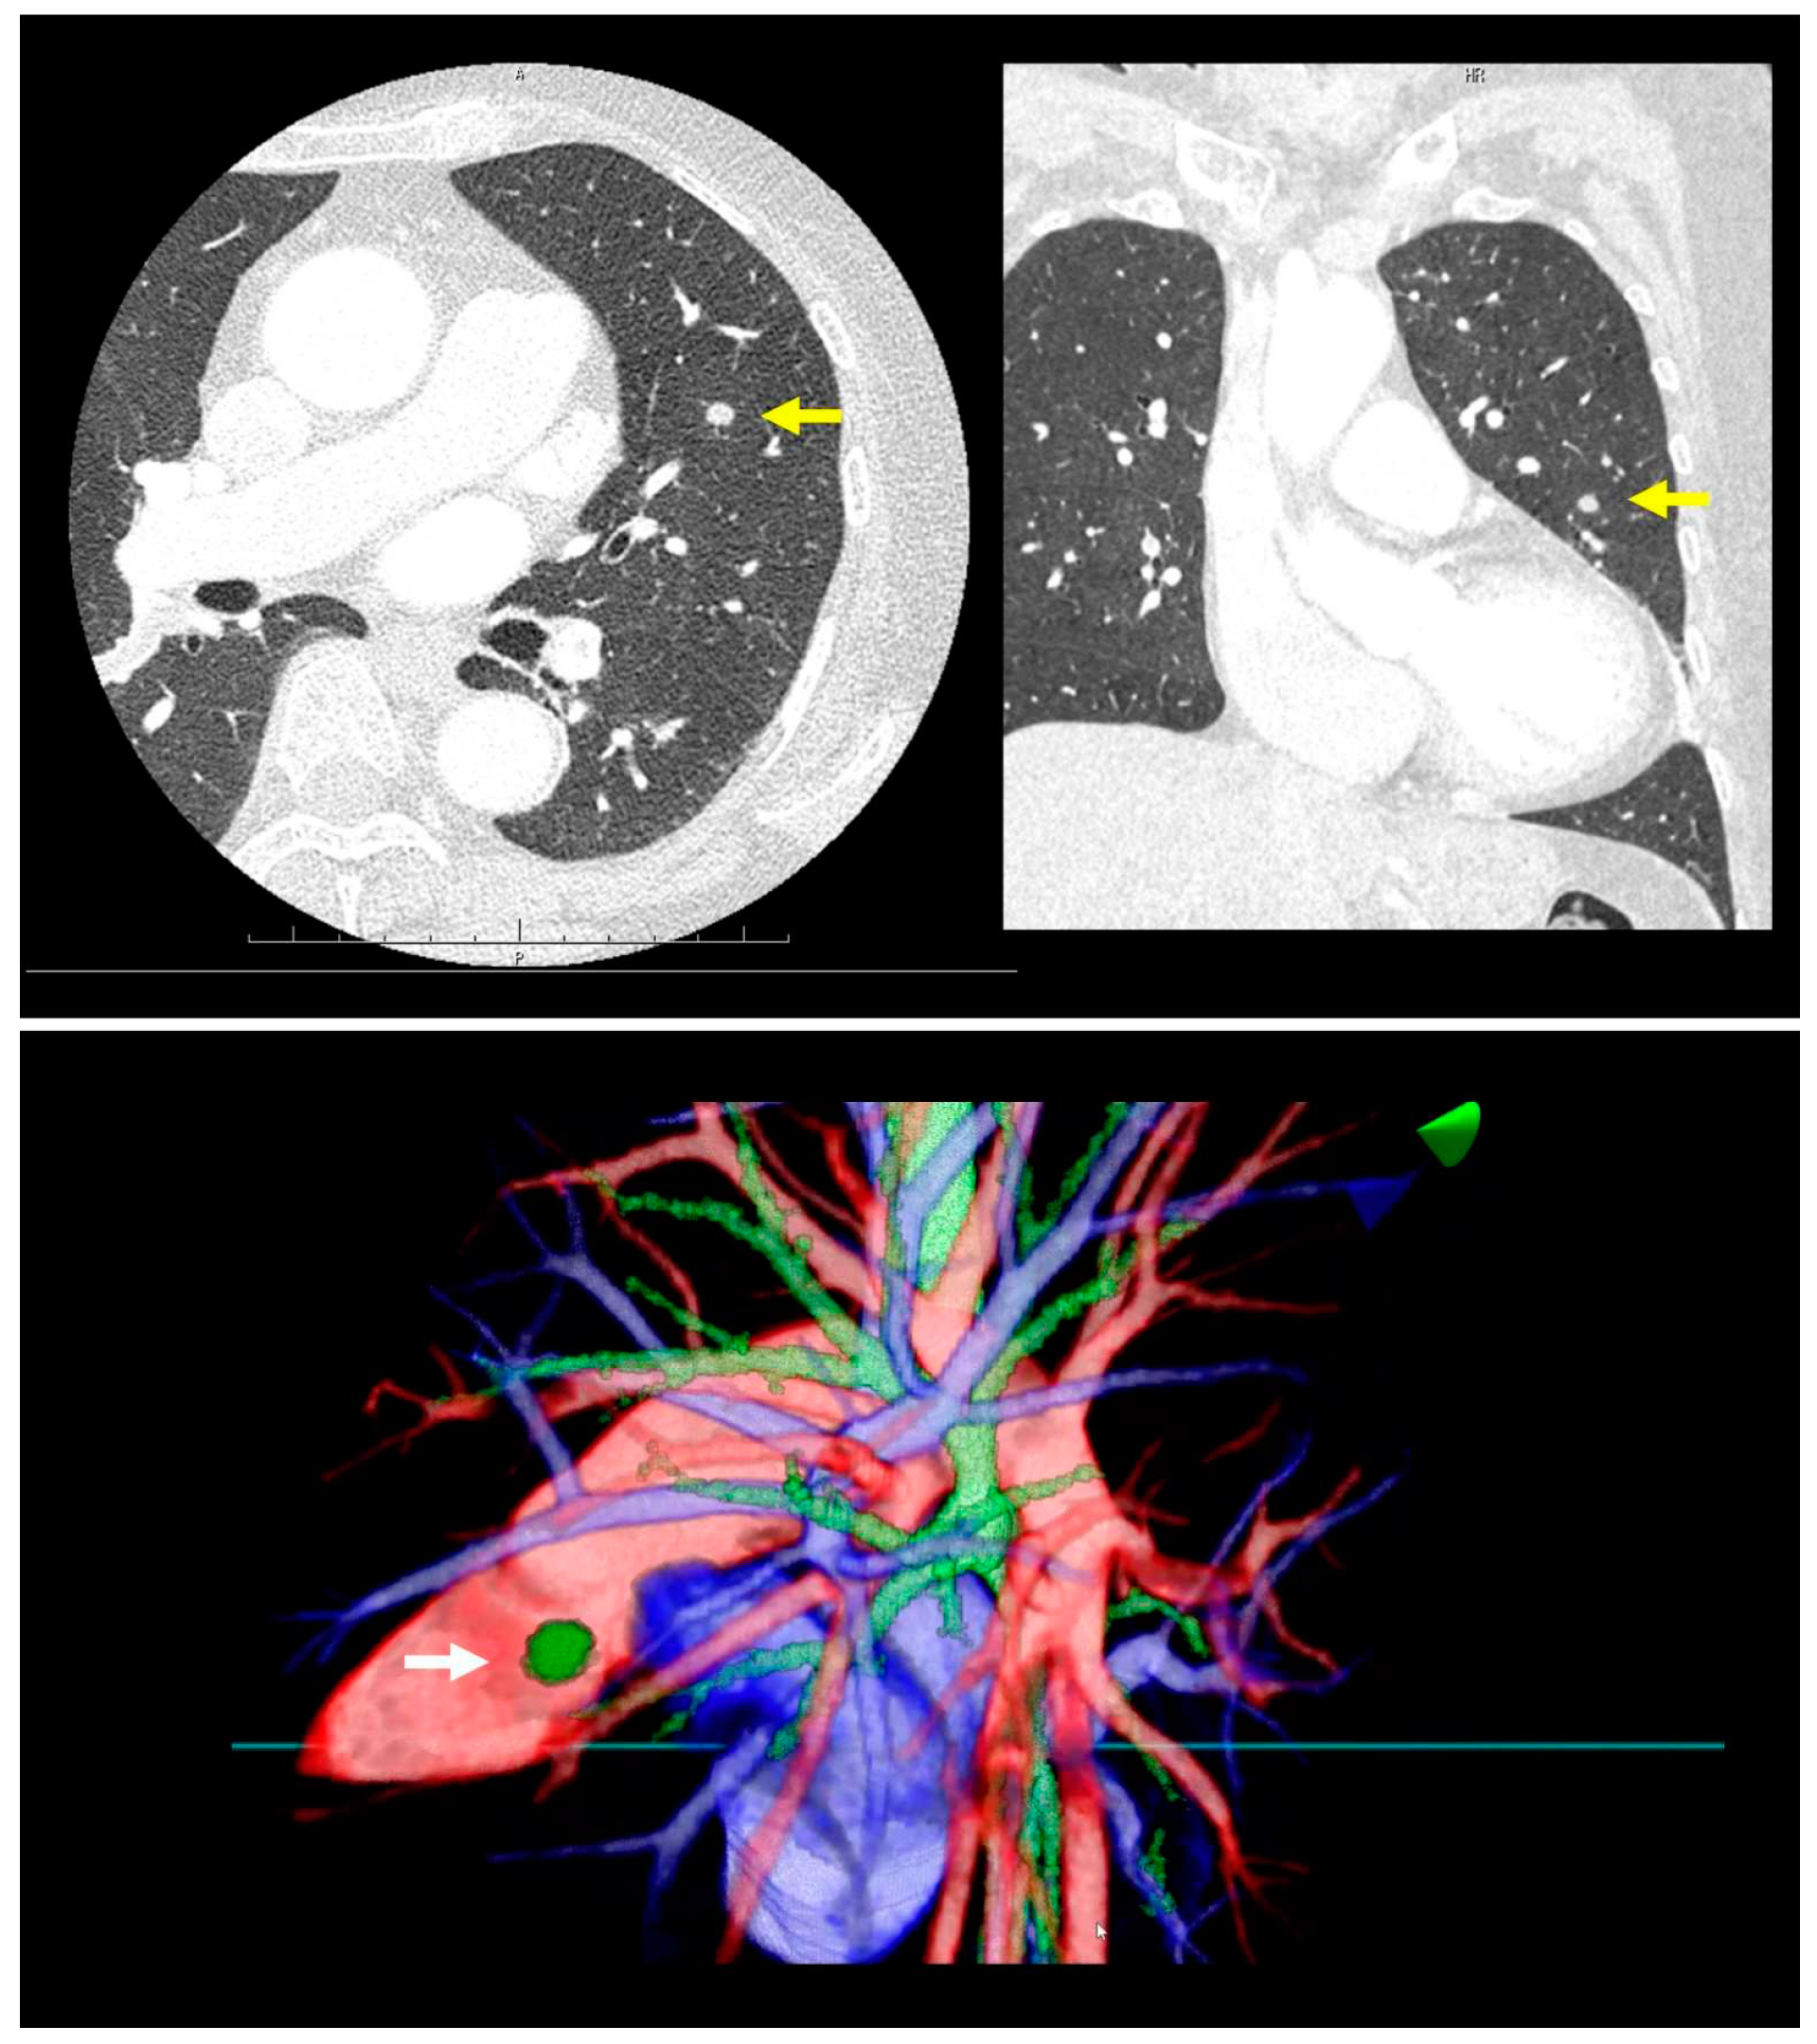

Prior to surgery, a thorough analysis of the surgical resection plan was conducted using patient-specific 3D images. For instance, in a case involving a left lingular tumor, the preoperative chest CT scan and subsequent 3D modeling clearly delineated the tumor's spatial relationship with surrounding pulmonary structures (as shown in Figure 1). During this review process, the surgeon utilized an HMD to immerse themselves in the virtual reality representation of the patient's anatomy. The use of hand device controllers enabled the surgeon to interact with the virtual objects in various ways, such as translating, rotating, scaling, cropping, or erasing parts of the model for a detailed examination.

Figure 1. A virtual dynamic image is meticulously generated from patient-specific three-dimensional computed tomography (3D-CT) data, providing a detailed and interactive representation of the patient's internal anatomy. The top row of images showcases a preoperative chest CT scan of a patient with a left lingular tumor. The bottom row of images presents representative views of the 3D model derived from the same CT data.